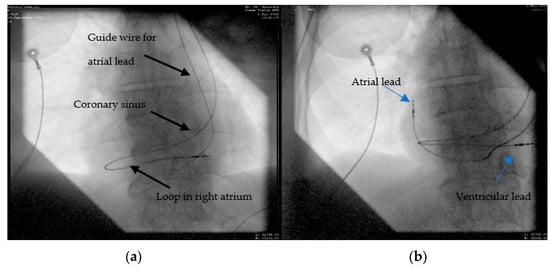

2.2. Case 2. (Type IIIa)